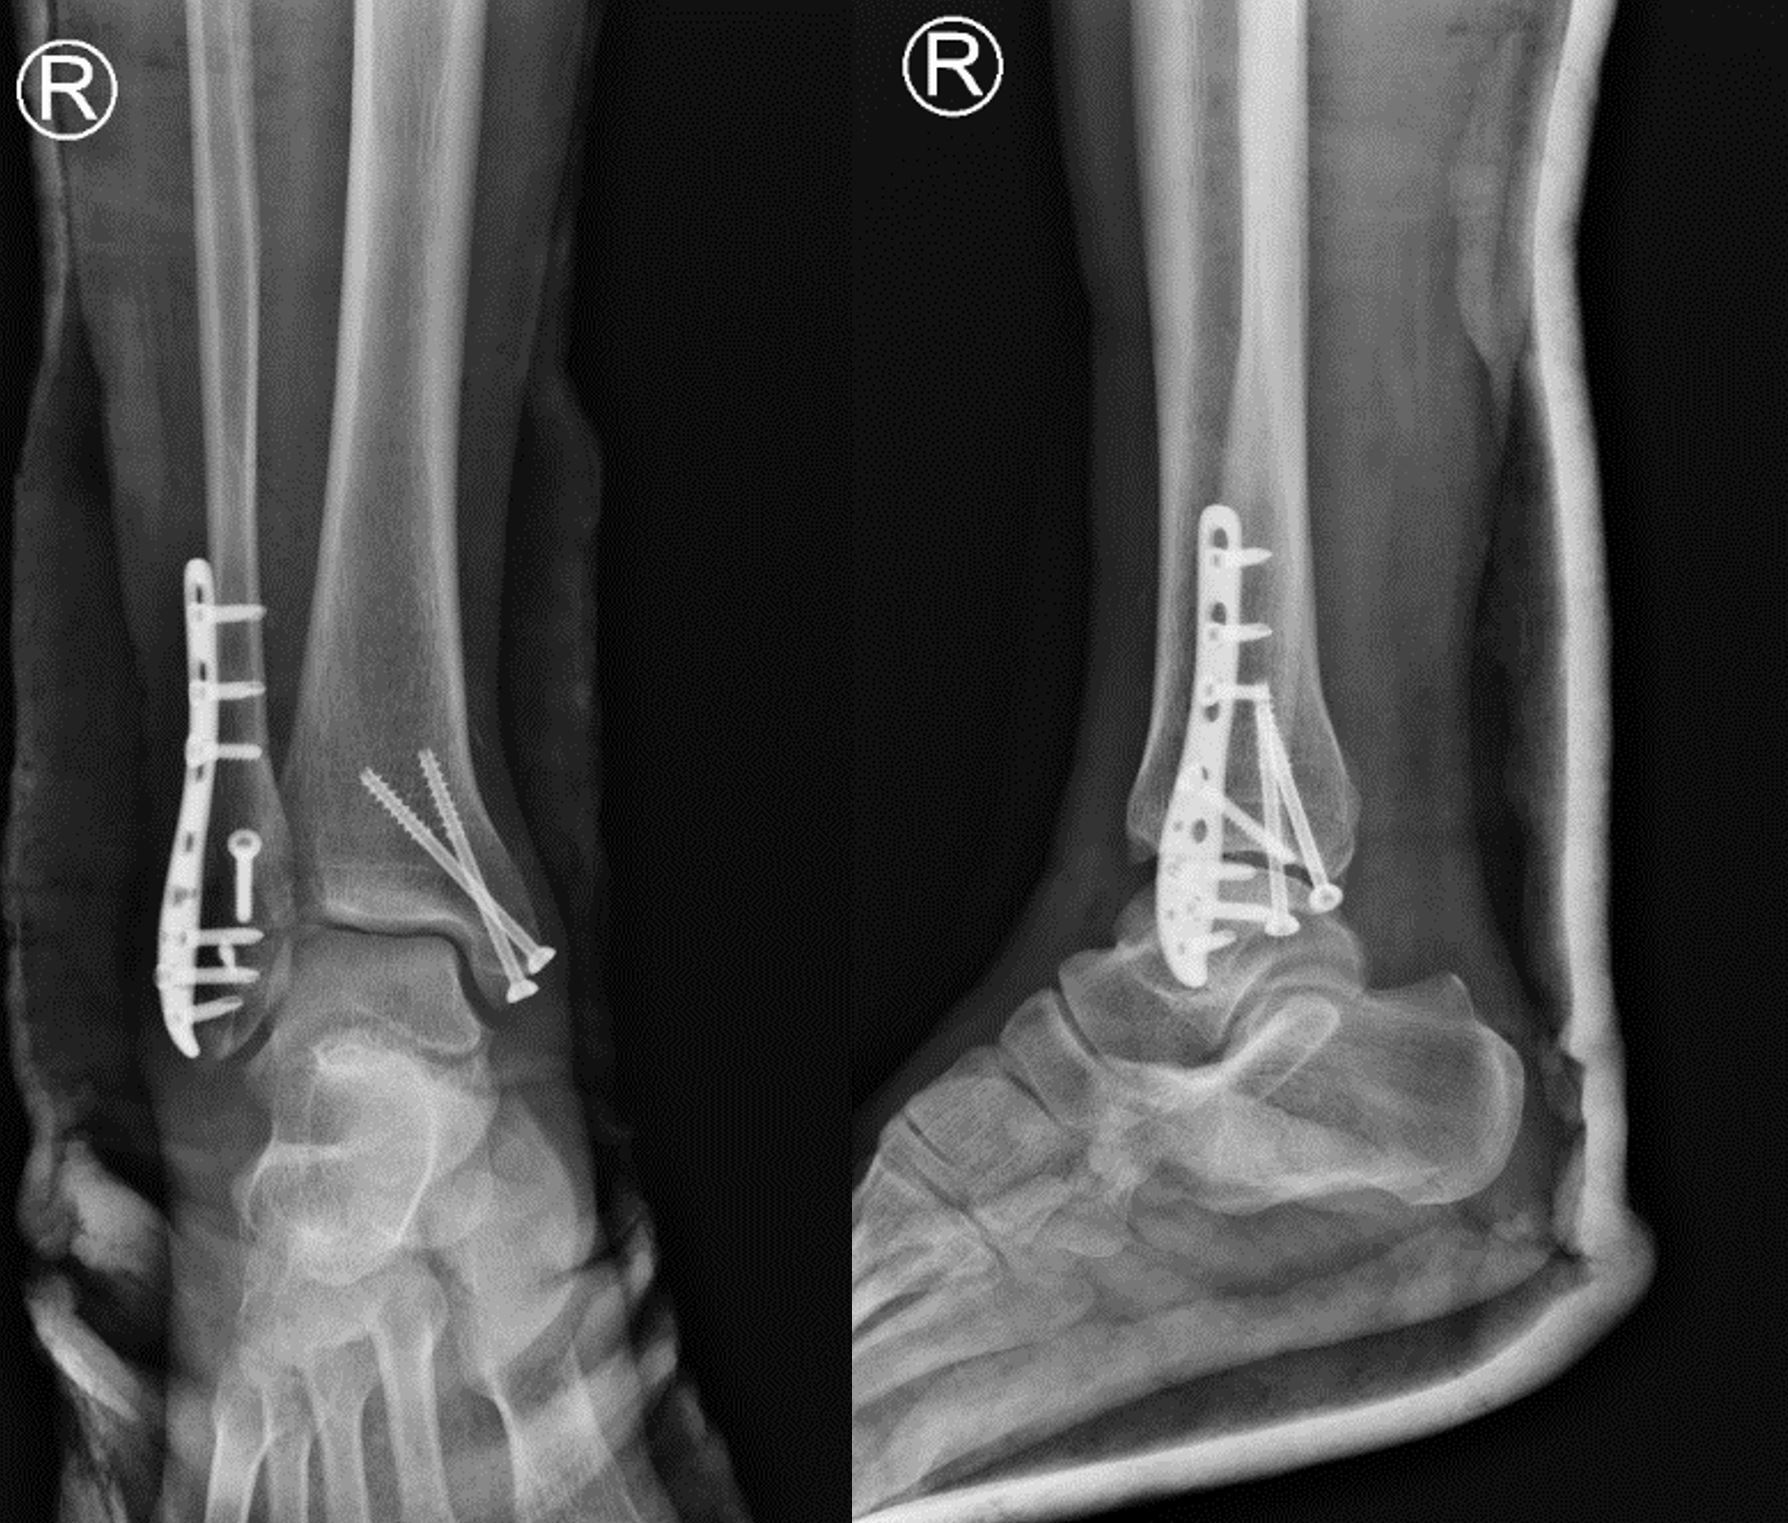

骨折复位固定照片